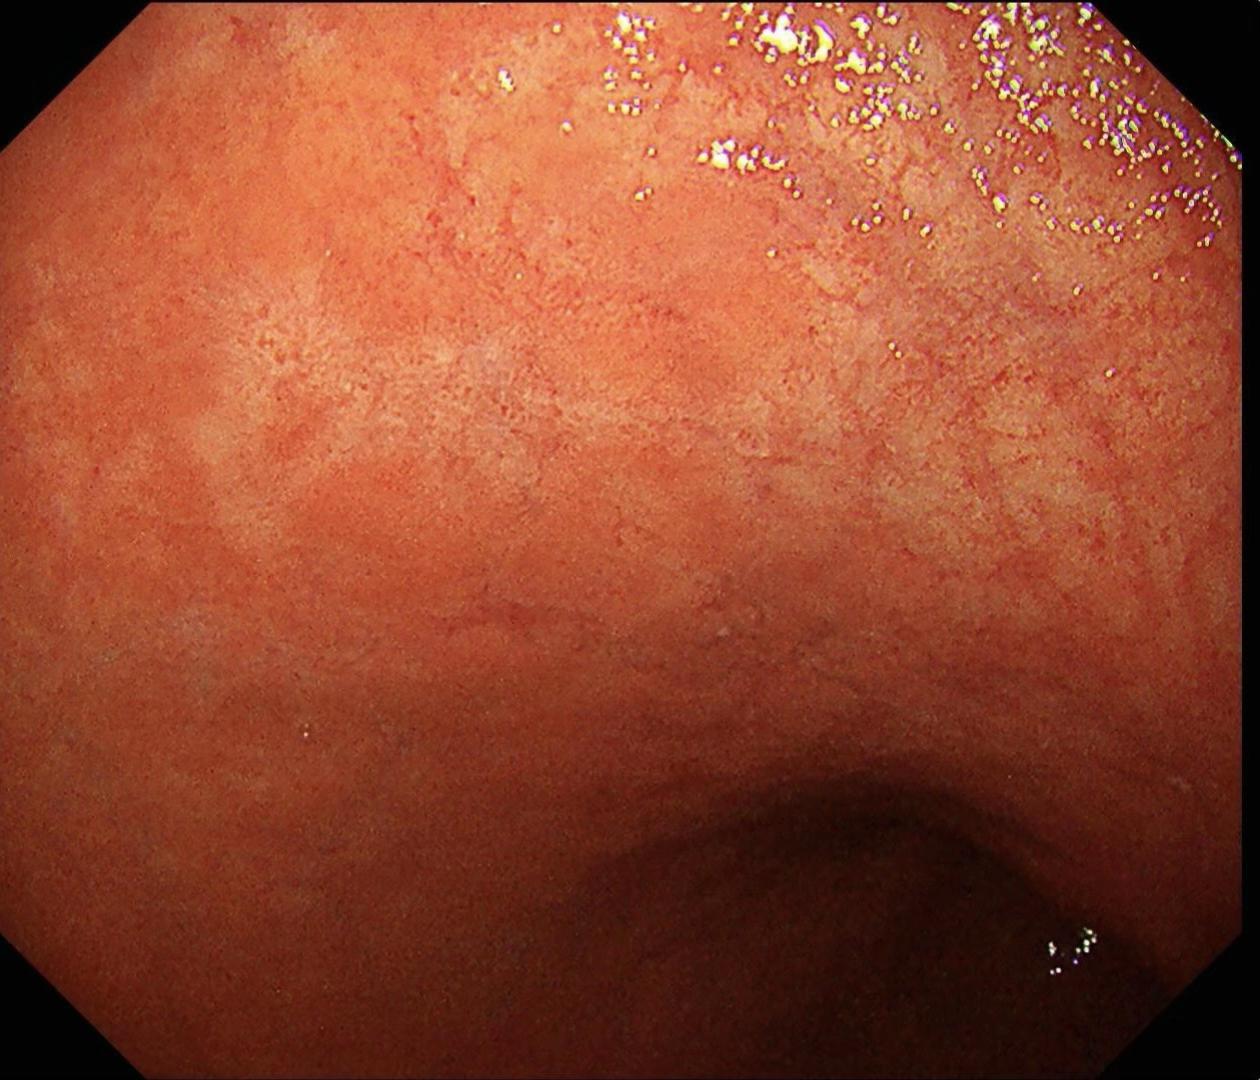

有段时间没见这么规则的网状血管了。好吧,我承认自己是个图控~

2025-08-09 13:02